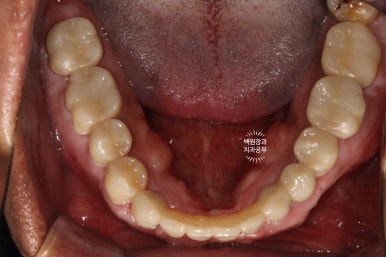

위 아래 교합면 사진입니다.

임플란트를 교합면에서 보았을 때, 잘 식립되어 있는 경우 저렇게 동그라미들을 보실 수 있습니다.

바로 screw hole 인데요, 추후 임플란트를 수리해야 할 일이 있을 때, 다시 개방하는 screw 입구입니다.

현재는 레진으로 메꿔져 있어요.

아래 어금니 지르코니아 크라운들도 해부학적 형태가 잘 재현되어 있고,

조화로운 모양과 색상으로 거의 자연치와 흡사한 형태를 보여주고 있어요.!!!